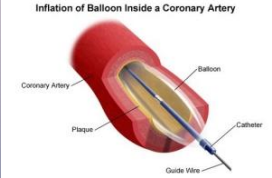

nonsurgical, flow, circulation, structural, balloon

Percutaneous Coronary Intervention (PCI)

-Minimally invasive ___________ procedure performed to improve blood ____ in one or more segments of coronary ___________

-Can be used for evaluation/interventional treatment for ___________ heart disease like adult congenital heart disease or valvular heart disease

-Most commonly used revascularization procedure

-Primarily involves the use of ________ angioplasty + intracoronary stenting

catheter, artery, blockage, widen, increase, stent

Balloon Angioplasty

-A specifically designed _________ is placed in a peripheral ______, and a tiny balloon is guided through the artery to a _________ within coronary circulation

-Balloon is inflated to _____ the opening and _______ blood flow to the heart. Part of PCI

-_____ is often placed during procedure to keep artery open after the balloon is deflated and removed